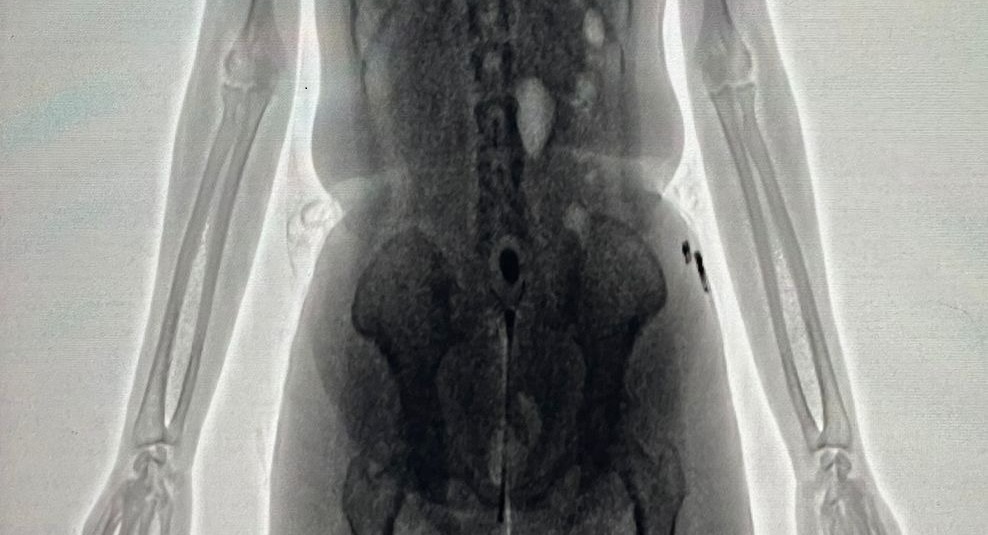

Ao passar pelo equipamento, policiais penais identificaram irregularidades na imagem corporal da visitante, companheira de um interno da unidade. As imagens apontaram a presença de um objeto em formato cilíndrico introduzido na cavidade pélvica.

Após a entrega espontânea do material, foi constatado que o objeto continha as substâncias ilícitas, acondicionadas em um único invólucro, envolto em fita preta. Segundo as informações, a aquisição da droga teria sido intermediada pelo custodiado, a quem o material seria entregue.